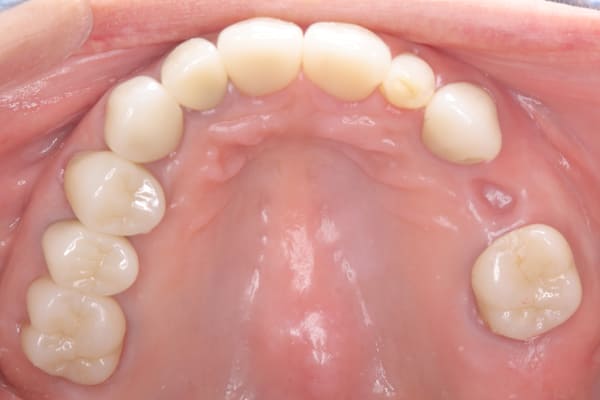

上顎治療後

下顎治療後

治療前の入れ歯の奥歯は、治療後の義歯と比較しても分かるように、歯が削れ平らになった状態です。

精密な型どりは、通常保険治療では使用しない、この患者様だけに合った型を取るトレーを作製、また寸法変化の最も少ない精密なシリコンを用いてお口の中を精密に限りなく再現する型どりの方法で型をお取りしました。

完成前に適合や見た目のチェックでは、咬む力で義歯がたわみ、残りの歯に負担がかからないよう、見えない内側は、金属を用い、強度を増し、また金属のため薄くすることで違和感をなくす設計とし、完成前に試し合わせを行い、装着感、審美性を確認しました。

治療用入れ歯は患者様とご相談し、早急にお痛みをとり、お食事ができることをご希望されていたため、歯を抜くと同時に仮の入れ歯が入りお食事をされた後のお写真です。直ちに、お痛みを取り除き、お食事ができるような治療計画としました。

精密義歯は、歯をぬいたあと歯肉が治ってから、精密な入れ歯を作製しました。治療中も、仮の入れ歯があるため、普段の生活に支障がなく、また仮の入れ歯を実際使ってのご意見、ご希望(バネが気になる)をお聞きした上で、精密な義歯に、ご希望を反映し作製しました。

従来の方法では、歯を抜いてから入れ歯を作るまでは、歯茎の治りを待つため数か月かかりますが、患者様のご希望で、見た目、食べることに支障が出ないよう、抜歯と同時に入れ歯を装着し、歯がない期間がない入れ歯を作製したため、その日から、お食事や外出が可能となりました。

また、当然ではありますが、患者様も残りの歯をこれ以上失いたくないとのご希望が強く可能な限り、残りの歯に負担がかからない機能性を重視し、また、バネがなるべく見えない設計とし、機能と審美の両方に重きをおいた入れ歯を作製し、お痛みなく、お食事も召し上がられるようになりました。